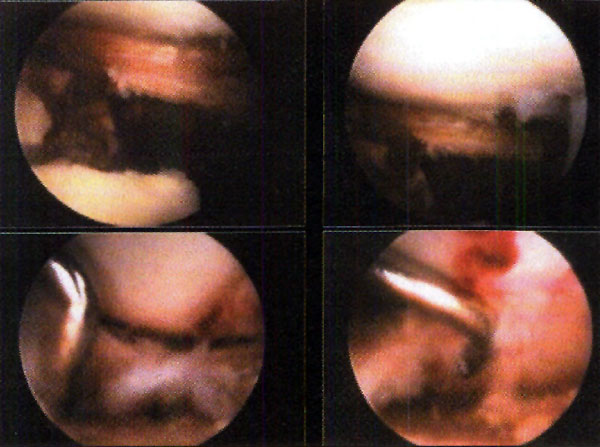

En las lesiones meniscales realizamos su sutura si la lesión es periférica (Fotos 1) o la menisectomía parcial si no reuniera condiciones de sutura. Las lesiones osteocondrales son tratadas con técnicas de estimulación mesenquimática, y en las lesiones de ligamentos cruzados, diferimos eventualmente su reconstrucción para un segundo tiempo quirúrgico. Luego de reconocer el trazo de fractura (localización, dimensiones, conminución, desplazamiento de los fragmentos, etc.) procedemos a su tratamiento. En las fracturas por hundimiento, realizamos una ventana ósea a nivel metafisodiafisario (aproximadamente 8 cm. por debajo de la línea articular ipsilateral a la fractura) a través de la cual introducimos un impactor romo (doble acodado a 90°), y procedemos a reducir los fragmentos hundidos mediante suaves golpes bajo visión artroscópica. (No utilizamos la guía tibial de ligamento cruzado anterior para ubicar la zona de lesión, dado que nuestros impactores son acodados y no canulados.)

Foto 1: Sutura meniscal

Los reparos utilizados para la reducción de la meseta tibial son el borde sano del cartílago y la cara inferior y el borde libre del menisco.(Fotos 2)

A medida que se corrige el hundimiento, controlamos mediante artroscopía si algún fragmento óseo se hipercorrige, reduciéndolo con el palpador o una cureta. (Fotos 3, 4, y 5 )

Foto 2: Parámetros de reducción de la fractura

Foto 3, 4 y 5: Control artroscupico de la reducción